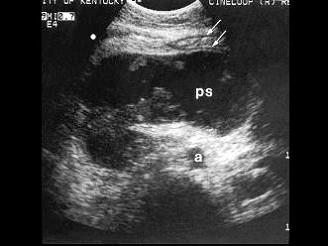

问题 患者女,56岁,急性胰腺炎1周。B超图像如图,诊断为?(?)

选项 A.胰腺假性囊肿 B.胰腺囊腺癌 C.小网膜囊肿 D.后腹膜占位 E.以上都不是

答案 A